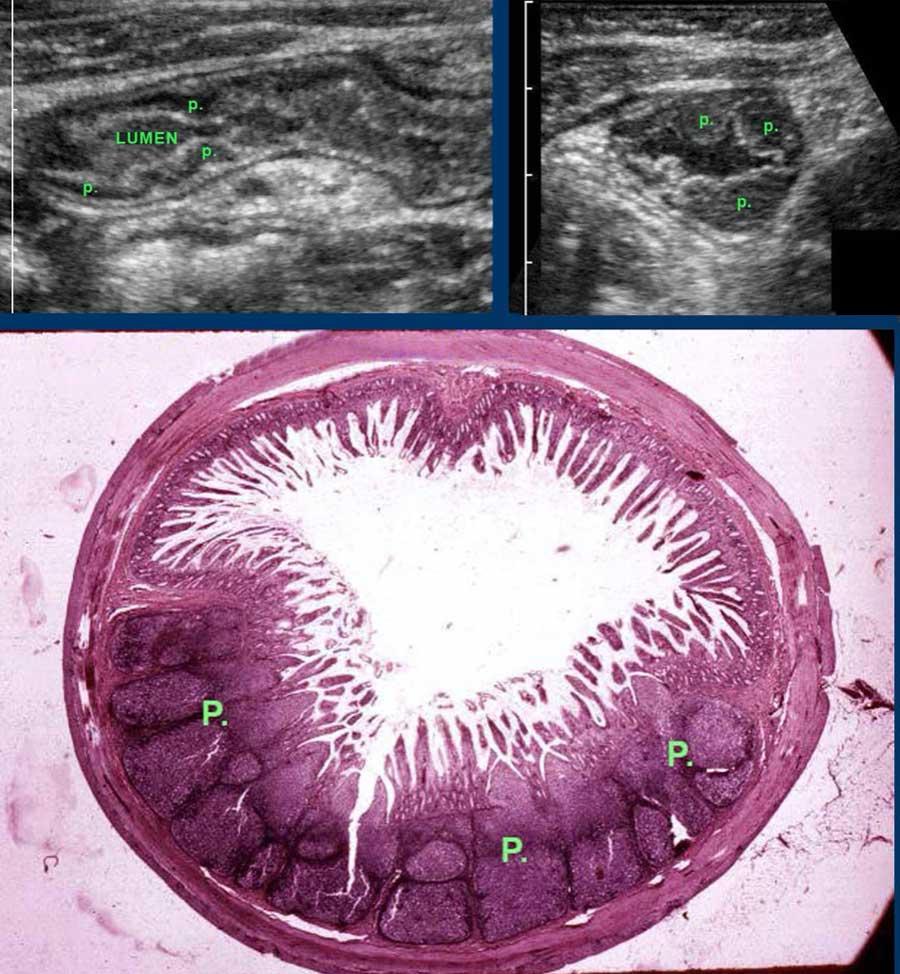

Đặc biệt ở hồi tràng tận của trẻ em và người trẻ tuổi, mô lympho giảm âm nổi bật được tìm thấy ở lớp niêm mạc sâu.

Các mảng Peyer (p) được gọi như vậy có thể rất lớn và không đối xứng.

Đây là hình ảnh của hồi tràng tận cùng ở ba trẻ em và người trẻ tuổi khác nhau với các mảng Peyer lớn biểu hiện dưới dạng dày lớp niêm mạc sâu không đối xứng, giảm âm.

Với mỗi kháng nguyên mới, mô bạch huyết lại được tái hoạt hóa.

Ở bệnh nhân trẻ tuổi, cả hạch bạch huyết mạc treo ruột và các mảng Peyer đều lớn hơn nhiều so với người trưởng thành – kể cả về kích thước tuyệt đối.